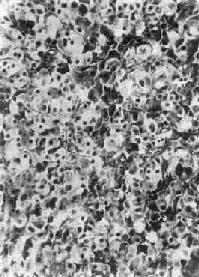

图15-16 肾上腺皮质腺瘤

上图 ×120 下图 ×280

肾上腺皮质腺瘤与局灶性结节性增生的病变相似,两者可以并发。腺瘤通常是单侧单发性,并有薄层包膜,对周围组织有压迫现象,为鉴别的主要点。大小直径为1~5cm,切面黄色,有时呈红褐色,镜下多为类似束状带的泡沫状透明细胞,含有丰富类脂质,有时由类脂含量少的嗜酸性细胞构成,或者两种细胞混合存在。瘤细胞排列成团,由含有毛细血管的少量间质分隔(图15-16)。部分腺瘤为功能性,可引起醛固酮增多症或Cushing综合征,在形态上与非功能性腺瘤没有区别。